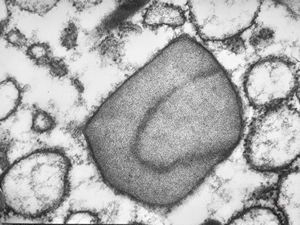

M,62y. | crystalline inclusion in endoplasmic reticulum - bone marrow, plasmocytoma

M,62y. | crystalline inclusion in endoplasmic reticulum - bone marrow, plasmocytoma

M, | crystalline inclusions in plasmocyte

M, | crystalline inclusions in plasmocyte

M,15y. | crystalline inclusion in plasmocyte - histiocyto-eosinophilic granuloma